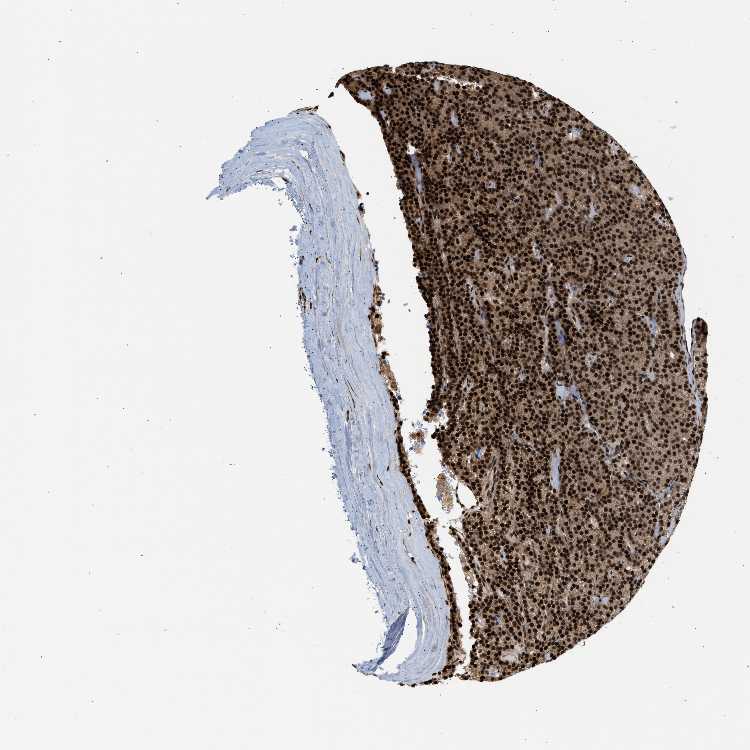

TISSUE PRIMARY DATA PARATHYROID GLAND Show tissue menu

PARATHYROID GLAND - Antibody stainingi

Antibody staining in the annotated cell types in the current human tissue is reported as not detected, low, medium, or high, based on conventional immunohistochemistry profiling in selected tissues. This score is based on the combination of the staining intensity and fraction of stained cells.

Each image is clickable and will lead to virtual microscopy that enables deeper exploration of all samples and also displays staining intensity scores, fraction scores and subcellular localization as well as patient and tissue information for each sample.

Antibody HPA017335Antibody HPA018011

Glandular cells HighHigh